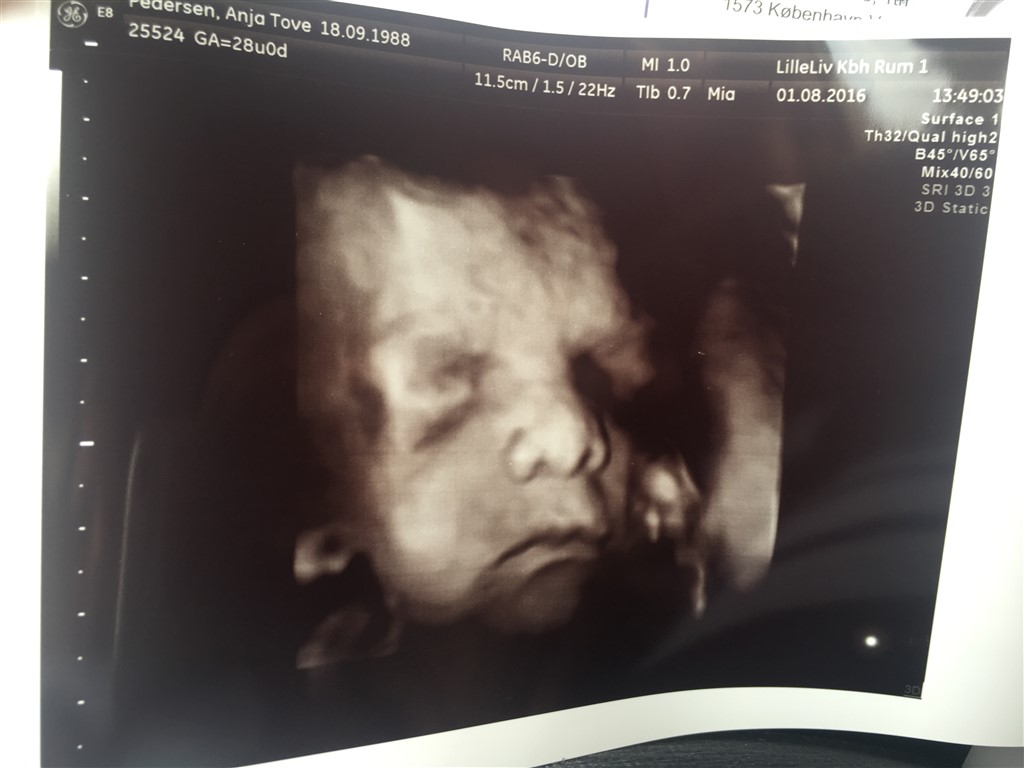

Vi har valgt gaver fra til hinanden og i stedet tog vi til 3D/4D skanning for at se til prinsessen

Hvilken fantastisk oplevelse! Hun startede med at have foden i hovedet, men hun var dog lidt sød og lagde sig anerledes så vi kunne se hendes smukke ansigt

Og nej hvor hun ligner sin far! Og dermed ligner hun altså også Isaac virkelig meget, ingen tvivl om hvem hverken far eller storebror er!

Billeder af maven bliver ikke denne gang, men af prinsessen i 3D

Vedhæftede fotos (klik for at se i fuld størrelse)